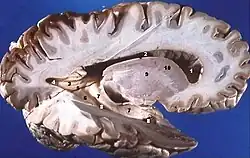

La substance blanche est une catégorie de tissu du système nerveux central, principalement composé des axones myélinisés des neurones. Elle relie différentes aires de la substance grise où se situent les corps cellulaires des neurones. Elle constitue la partie interne du cerveau et la partie superficielle de la moelle épinière.

Dans le cerveau, on trouve différentes structures de substance blanche :

- Les capsules externes

- Les capsules internes

- Les capsules extrêmes

- Le chiasma optique

- Le centre ovale de Vieussens

- La commissure antérieure

- La commissure postérieure

- Le corps calleux ou mésolobe

- Les trigones ou fornix